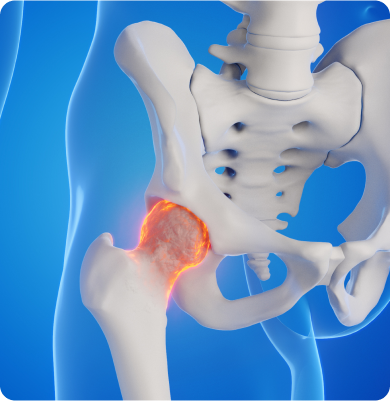

골괴사증(대퇴골두)

뼈에 혈액 공급이 부족해 뼈 조직이 죽고 그로 인해 뼈가 약해지고 변형되는 질환

주요증상

• 엉덩이나 고관절에 통증이 발생하며 걷거나 움직일 때 통증이 심해질 수 있습니다.

• 고관절의 움직임이 제한되어 다리의 강직 현상이 나타날 수 있습니다.

• 다리 길이가 비정상적으로 짧아지거나 불균형이 생길 수 있습니다.